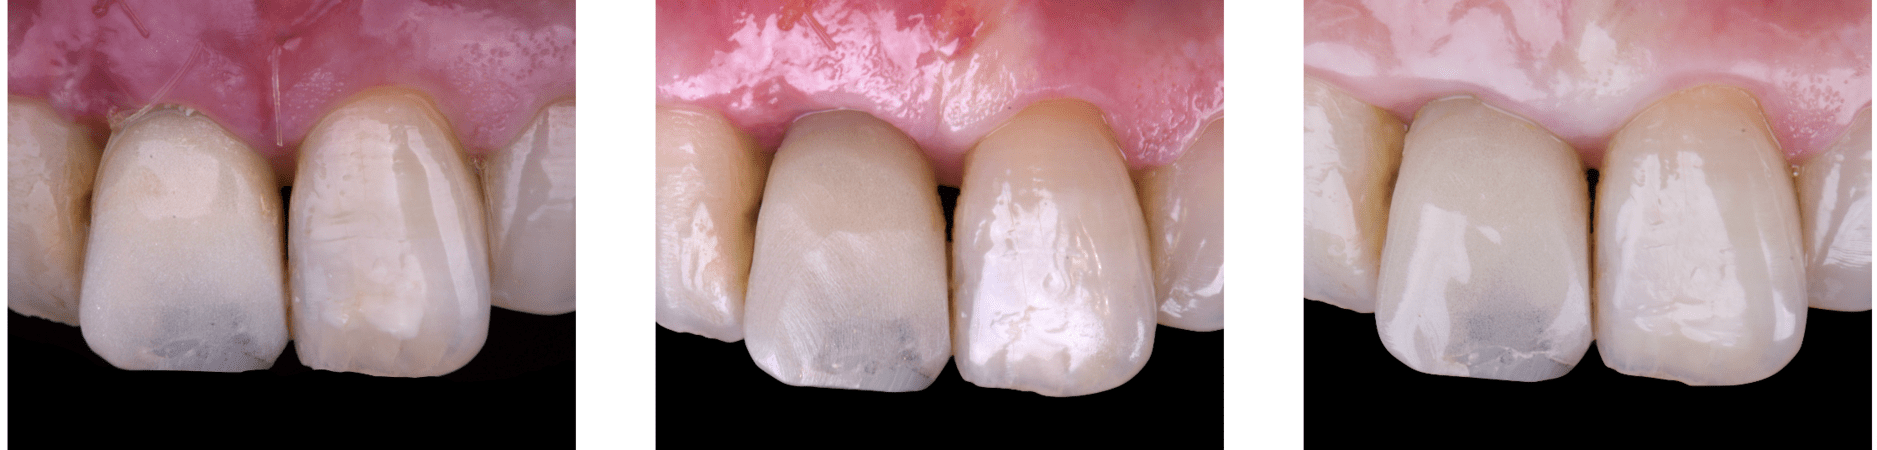

On the same day as the surgery, an immediate-load provisional crown was delivered. This restoration was fabricated in acrylic resin and screw-retained on the implant, following the “one abutment one time” principle. The provisional crown was carefully adjusted to avoid occlusal loading while supporting the peri-implant soft tissue architecture during the healing phase.

The provisional not only satisfied the patient’s functional and esthetic demands but also played a key role in shaping the emergence profile and conditioning the gingival margin. By providing a provisional solution immediately, the patient was able to leave the clinic with a natural-looking smile, avoiding any psychological or social impact associated with tooth loss in the anterior maxilla.

After an appropriate healing period, the definitive prosthesis was planned and delivered. A screw-retained zirconia crown was fabricated to ensure long-term durability, optimal esthetics, and retrievability. Zirconia was selected for its mechanical strength and excellent esthetic properties, blending seamlessly with the adjacent natural dentition in both form and color.

The final crown was designed to maintain the gingival architecture that had been shaped by the provisional. Special attention was paid to the emergence profile, contact points, and translucency to achieve harmony with the patient’s smile. The definitive restoration provided functional stability and esthetic integration, fulfilling the patient’s expectations for a fixed and natural solution.